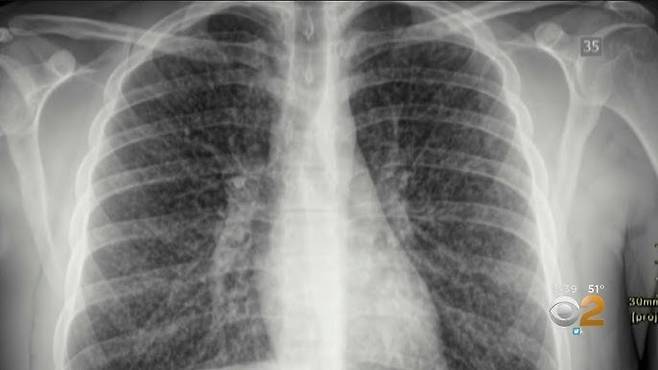

![팝콘 폐(popcorn lung). [CBS]](https://img4.daumcdn.net/thumb/R658x0.q70/?fname=https://t1.daumcdn.net/news/202504/10/ned/20250410143658611pthx.jpg)

‘팝콘 폐’는 폐의 세기관지가 염증으로 상처가 생기고 위축되면서 산소의 흐름이 줄어드는 치명적인 폐질환이다. 전자담배의 합성 향료 성분인 디아세틸을 장기간 흡입하면 발생할 수 있는 것으로 알려져 있다. 현재까지 폐 이식 외에는 별다른 치료법이 없다.